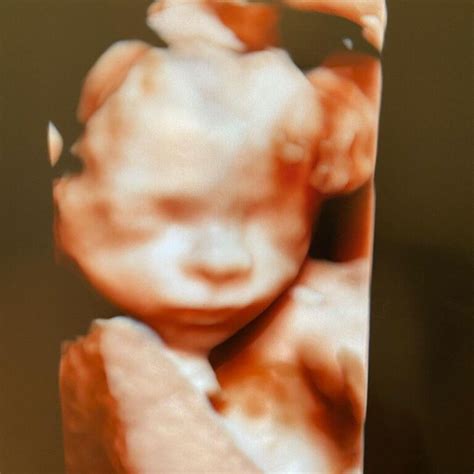

Un alt moment extrem de așteptat de părinți este când se vede sexul copilului la ecograf. În general, sexul fătului poate fi identificat cu precizie începând cu săptămâna 18. Totuși, se poate greși sexul copilului la ecograf în anumite situații. În acest caz, medicul va anunța sexul cu o anumită probabilitate și va sugera reprogramarea ecografiei pentru o confirmare ulterioară. 80% din examinarea ecografică propriu-zisă se realizează în modul 2D, însă ecograful cu capabilități 3D/4D sporește calitatea imaginii 2D analizate de medic cu până la 40%; Modulul de examinare în 3D/4D este folosit la finalul detalierii morfologice. Softul 3D/4D ne oferă imagini tridimensionale cu fătul în timp real, ce pot fi oferite pacientei pe CD.

Există două tipuri principale de ecografii folosite în sarcină. Ecografia transvaginală este folosită în primele săptămâni de sarcină. Ecografia abdominală este o metodă clasică, în care medicul aplică un gel pe abdomen, iar medicul folosește o sondă pentru a crea imaginea fătului. Morfologia fetală de trimestrul II poate fi realizată 2D (oferă cele mai multe detalii privind anatomia fetală), 3D, 4D (are mai puțin valoare diagnostică, dar oferă imagini mult mai clare). 80% din examinarea ecografică propriu-zisă se realizează în modul 2D, însă ecograful cu capabilități 3D/4D sporește calitatea imaginii 2D analizate de medic cu până la 40%. Modulul de examinare în 3D/4D este folosit la finalul detalierii morfologice. Softul 3D/4D ne oferă imagini tridimensionale cu fătul în timp real, ce pot fi oferite pacientei pe CD. Dr. Cristian Nicolae, medic primar Radiologie și Imagistică Medicală explică rolul Ecografiei de Sarcină 3D/4D, ca element complementar Ecografiei de Sarcină 2D. Mămicile trebuie să știe că softul 3D/4D crește cu până la 40% performanța modulului 2D, dar modulul 2D rămâne singura modalitate de analiză a dezvoltării anatomice a fătului.

ROL EMOȚIONAL: „Ecografia 3D/4D reprezintă un beneficiu atunci când se dorește identificarea anumitor detalii și atunci când părinții sunt nerăbdători să-și vadă copilul din burtică și să-i analizeze trăsăturile! Aceasta creează un efect video live, similar unui film, cu bebelușul din burtica mamei și este o modalitate de apropiere a părinților de viitorul lor copil. Mai ales că, imaginea obținută prin examinarea 3D/4D de la 32-34 de săptămâni de sarcină este identică cu cea a bebelușului pe care mama îl ia în brațe după naștere.” ROL EDUCATIV: „Această examinare permite evidențierea și înțelegerea de către părinți a eventualelor malformații ale fătului - membre, coloană vertebrală, față, craniu. Ele pot fi mult mai ușor arătate și explicate părinților. Ecografia 3D/4D nu constituie o metodă de diagnostic a problemelor de sănătate ale copilului, însă poate contribui cu informații suplimentare privind o anormalitate deja constatată în timpul ecografiei 2D.”

Ecografia de sarcină 3D este o investigație superioară ecografiei 2D. Se utilizează pentru depistarea anomaliilor fetale. Investigația permite reconstrucția imaginii în 3 dimensiuni spațiale. Astfel, putându-se vizualiza mult mai eficient toate detaliile anatomice ale fătului. Ecografia 4D adaugă un element în plus: sunt surprinse imagini ale fătului care cască, se răsucește, clipește sau chiar zâmbește. Se poate vedea expresia feței, culoarea ochilor. Ecografia 3D și 4D folosesc aceeași tehnologie ca și ecografia 2D, prin urmare sunt la fel de sigure pentru mamă și copil. Spre deosebire de razele X și tomografii, ecografiile nu utilizează radiații.

În urma morfologiei fetale, vei primi gratuit un CD cu imagini din timpul sarcinii ce conțin capturi utile medicului ginecolog, dar și fotografii pe care le poți păstra ca amintire. „Ecografia 3D/4D reprezintă un beneficiu atunci când se dorește identificarea anumitor detalii și atunci când părinții sunt nerăbdători să-și vadă copilul din burtică și să-i analizeze trăsăturile! Aceasta creează un efect video live, similar unui film, cu bebelușul din burtica mamei și este o modalitate de apropiere a părinților de viitorul lor copil. Mai ales că, imaginea obținută prin examinarea 3D/4D de la 32-34 de săptămâni de sarcină este identică cu cea a bebelușului pe care mama îl ia în brațe după naștere.”